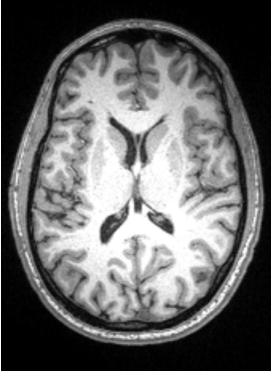

In the brain, ___ matter is the outer layer that contains cell bodies of neurons (projection and small interneurons) and ____ matter is the inner layer with ____ axons

Outer, Inner , myelinated

CSF is inside the ______ and helps (3)

Ventricle